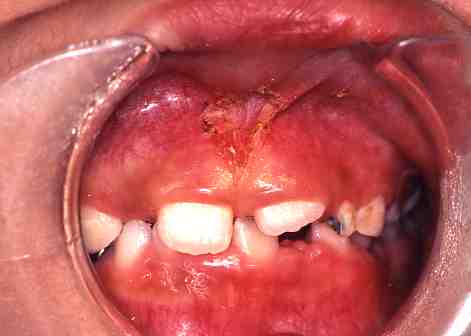

(3)小帯切除

1.術前

上唇小帯のスジが

張っています。

2.術後

この症例は麻酔をして

レーザーにて切除しました。

出血はまったくありませんでした。